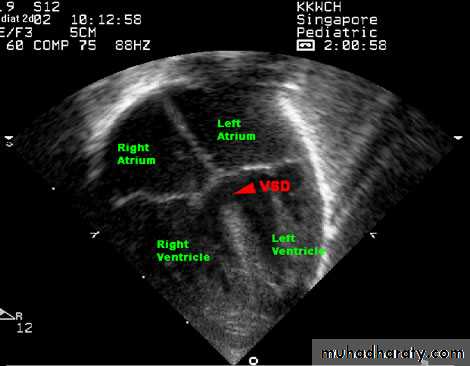

Echocardiography.

Two-dimensional and Doppler echo studies can identify the number, size, and exact location of the defect; estimate PA pressure; identify other associated defects; and estimate the magnitude of the shunt.